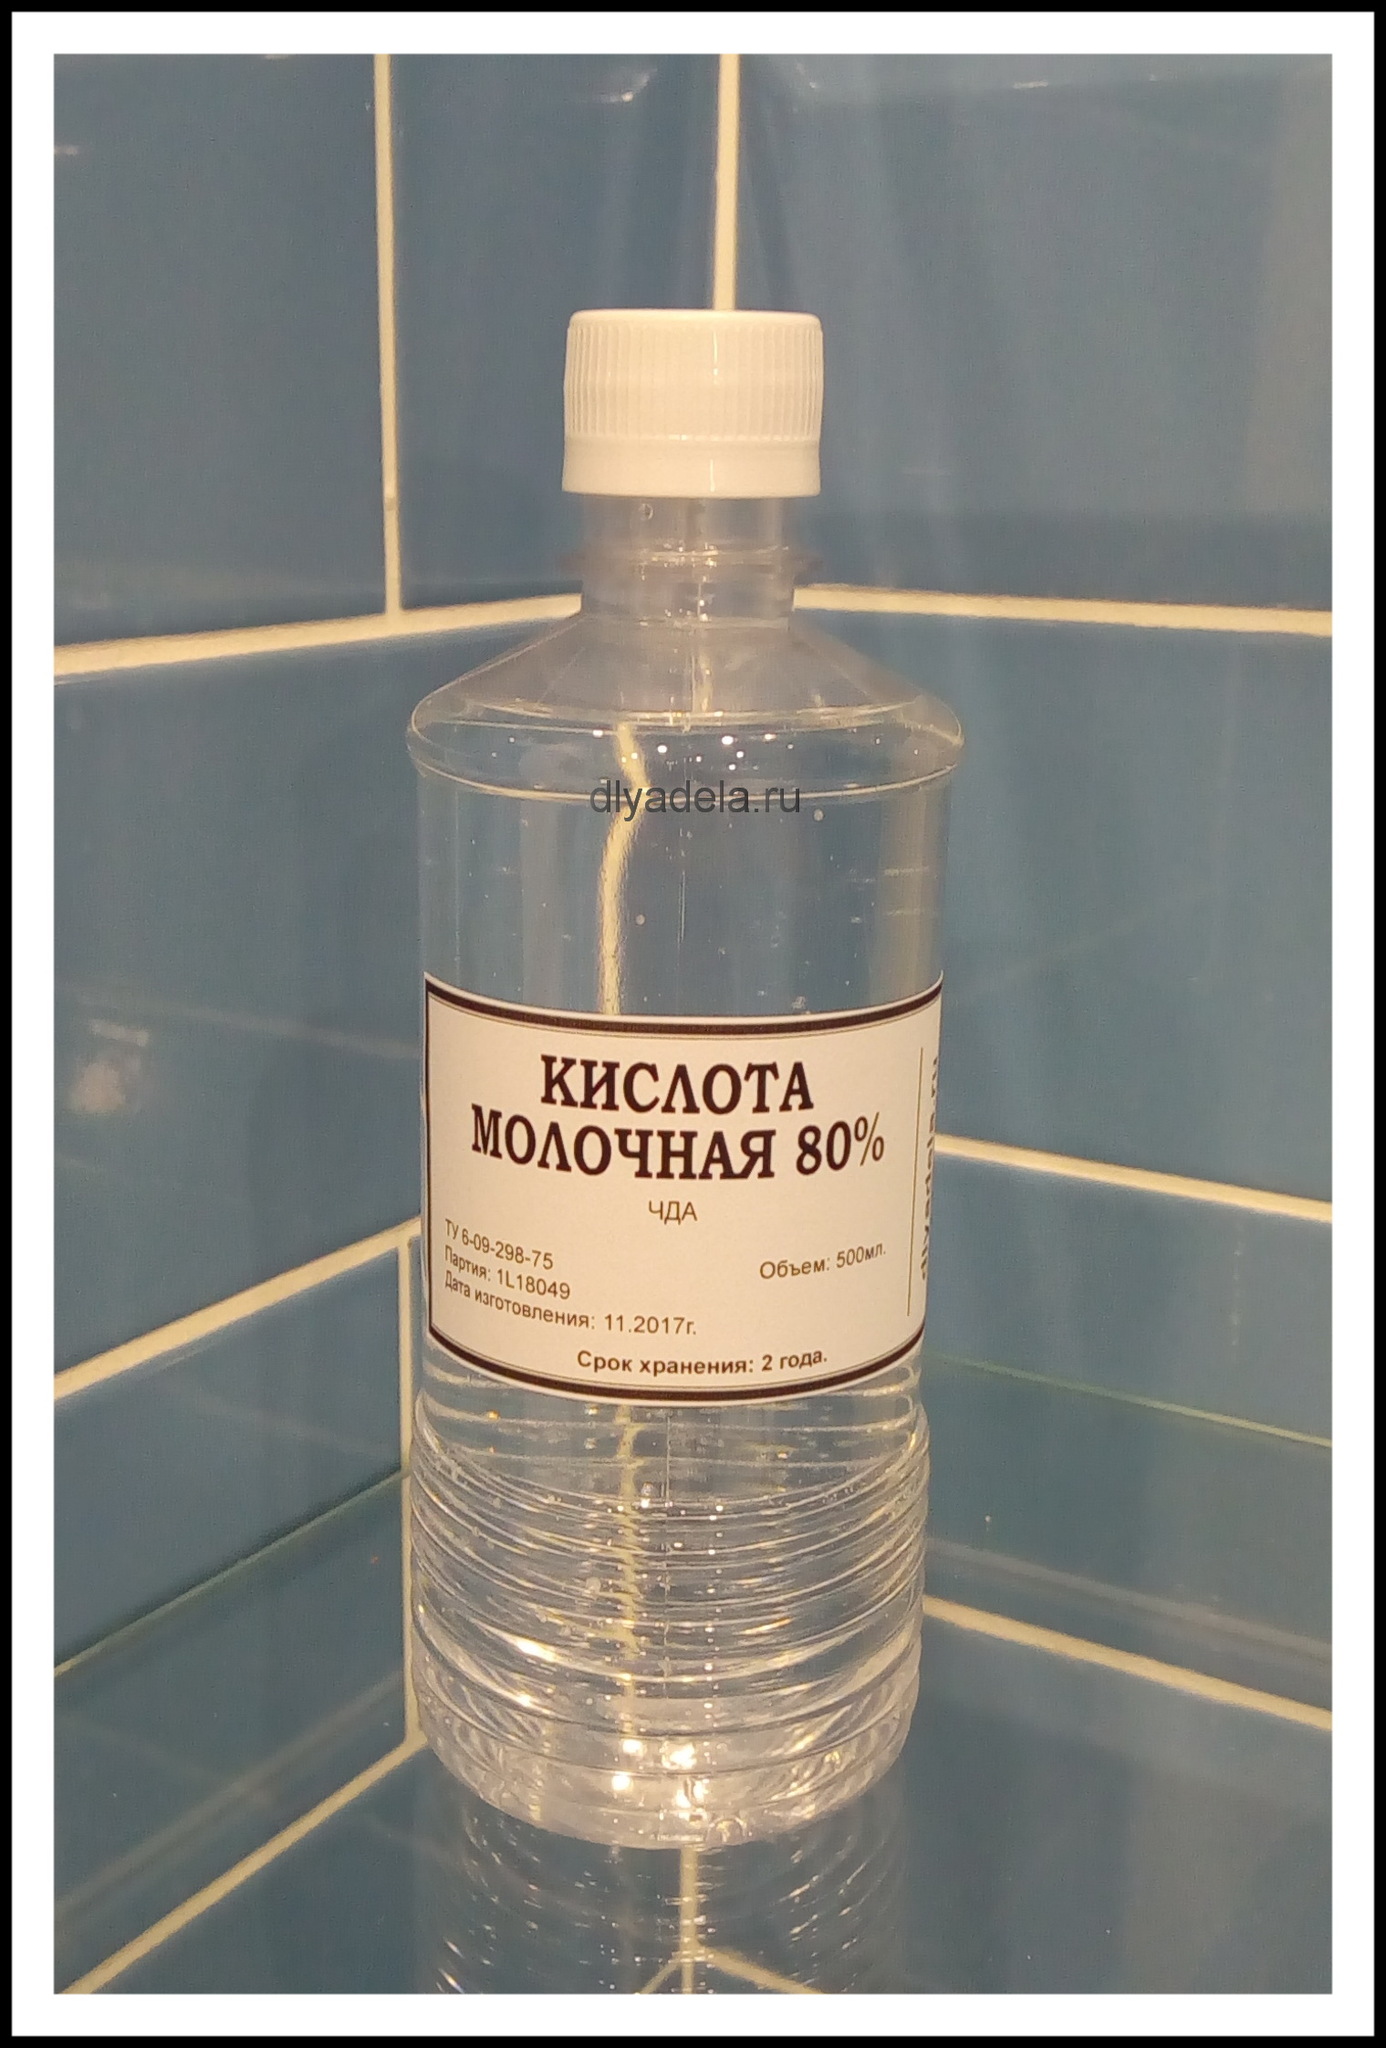

Молочная кислота в мышцах - это обычное явление, которое происходит в результате физических нагрузок. Она образуется в мышцах во время интенсивных тренировок, когда организм не может обеспечить достаточное количество кислорода для процесса окисления глюкозы. Это приводит к накоплению молочной кислоты в мышцах, что может вызвать ощущение жжения и усталости.

Молочная кислота может вызвать ощущение усталости и дискомфорта в мышцах во время и после тренировки. Однако, это является естественной реакцией организма на интенсивные нагрузки. Со временем мышцы адаптируются к процессу накопления молочной кислоты, что позволяет улучшить выносливость и способствует росту мышечной массы.